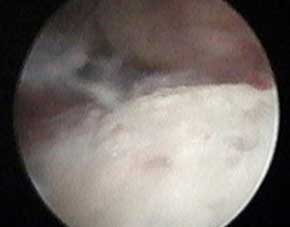

- 类风湿检查

针刀镜技术内窥镜下,可见类风湿患者关节内大量血管翳和滑膜增生